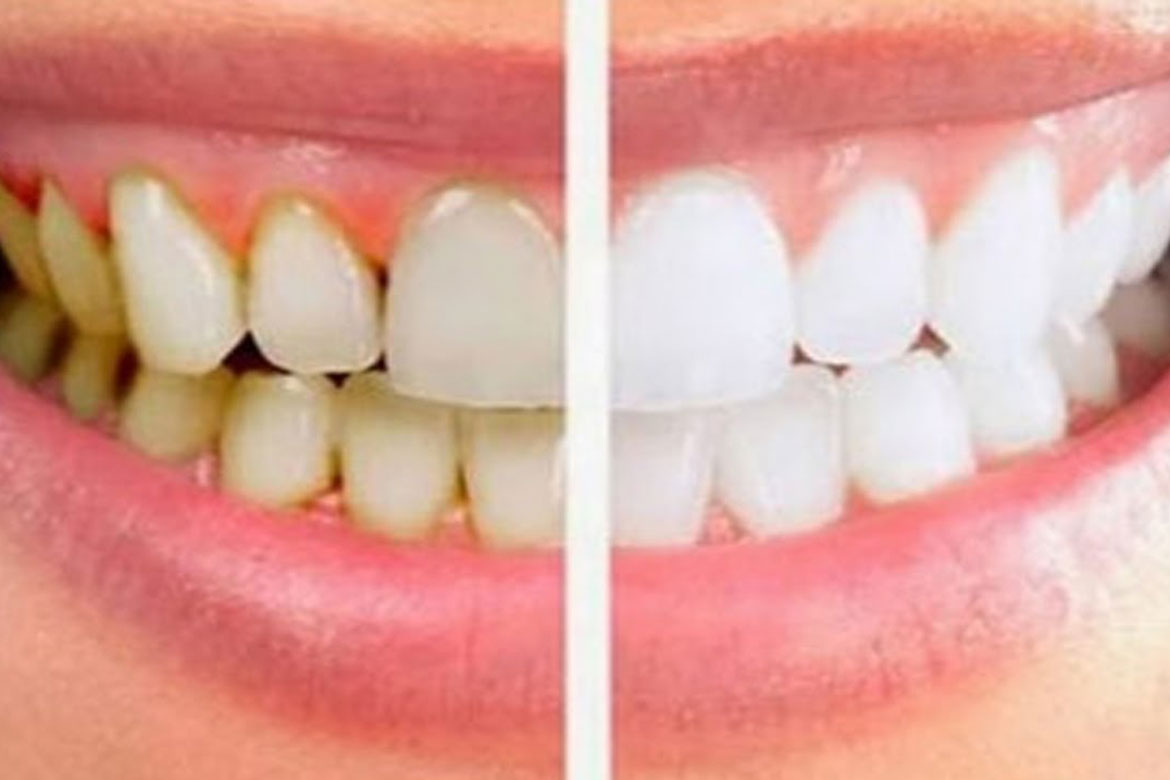

Plaques et tartre